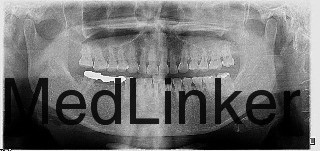

X-ray显示根管治疗不完善。

治疗方案:方案一:拔除21后种植修复。

方案二:拆除不良修复体,重新治疗后桩冠修复。

患者拒绝拔牙选择方案二